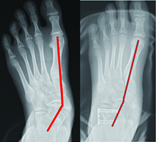

如骨骼發育已接近完成的青少年(一般為上國中以後)或是扁平足變形程度較大的兒童,考慮手術矯正時,則需施行跟骨延長矯正手術(圖四),較能達到良好的矯正效果。

圖四、跟骨延長術前與術後,前足外翻獲得良好的矯正